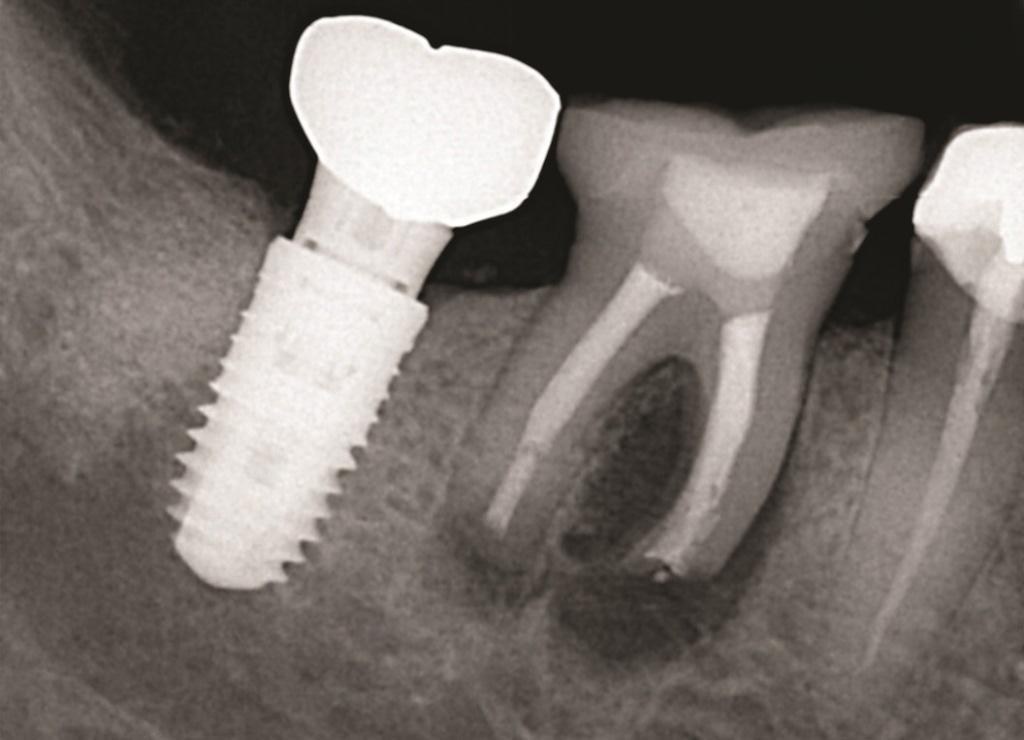

К таким патологическим состояниям относятся вертикальные переломы корней, перфорации корней, пародонтит с поражением корней из-за проблем в области фуркации или сближения корней, сочетанные эндодонтическо-пародонтальные дефекты на фоне коротких корней, устойчивые фуркационные дефекты, значительные не поддающиеся лечению внешние резорбтивные дефекты и другие (Фото 1–4). Когда подобные состояния затрагивают однокорневые зубы, удаление часто является единственным способом устранения патологии. Однако в случае многокорневых зубов существует дополнительная возможность: полное удаление источника патологии с одновременным сохранением функциональности зуба, что демонстрирует опубликованные показатели выживаемости на уровне 80–90%. При правильном выполнении с учетом описанных в статье факторов такое функциональное состояние может сохраняться в долгосрочной перспективе со средним сроком службы от 6 до 20 лет.

Фото 4: 3D-изображение КЛКТ зуба 1.6, демонстрирующее апико-маргинальный дефект кости, затрагивающий мезиально-щечный корень при стабильных сросшихся дистально-щечном и небном корнях.